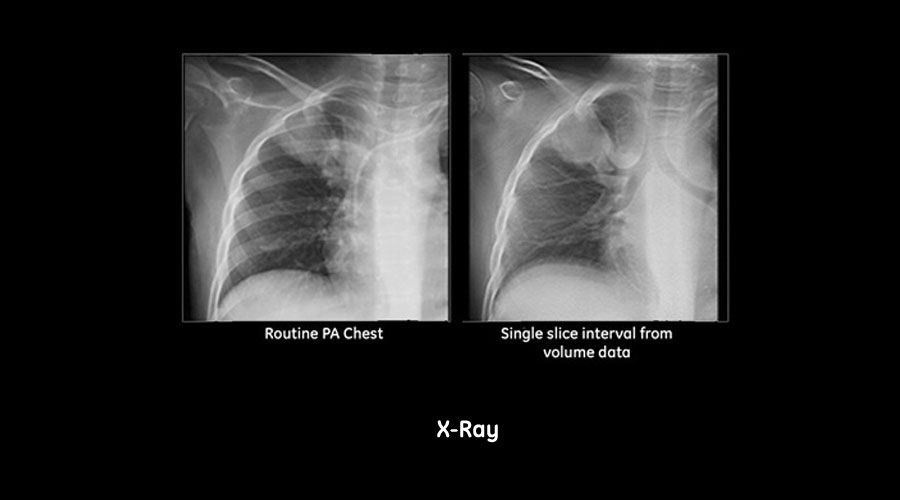

Today orthopedic specialists rely on standard radiography for diagnosing skeletal trauma, monitoring bone union, and evaluating the success of surgical interventions.

Advanced medical imaging is often ordered for complex cases that radiography cannot solve. These additional imaging modalities may result in higher radiation exposure, higher imaging costs, and a delay in diagnosis & treatment that could also mean more anxiety and discomfort for the patient. VolumeRAD digital tomosynthesis can be used to detect and monitor complex fractures and implants whilst being competitive when compared to other imaging modalities on radiation dose, workflow and economics.

- See how digital tomosynthesis compares to other imaging modalities on

radiation dose, workflow and economics - Review clinical cases where VolumeRAD is used to detect and monitor

complex fractures and implants